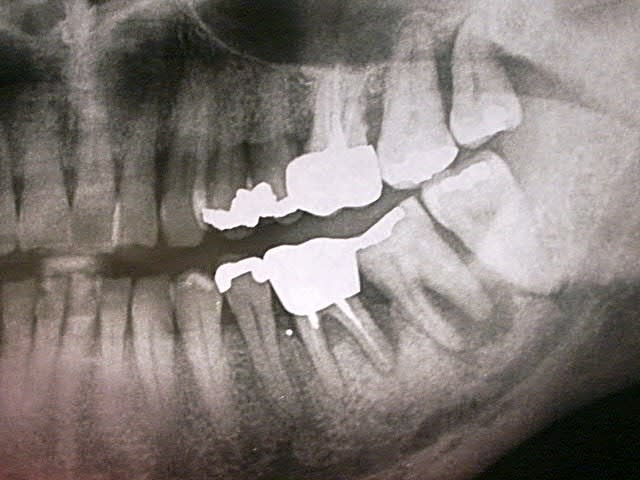

Manifestement alvéolyse horizontale généralisée, 25% de perte d'attache à 65 ans : je penche pour une parodontite chronique de l'adulte.

Suffisant s'il n'y avaient pas ces facteurs aggravants que sont les pulpectomies déficientes, couronnes débordantes et mal ajustées.

Je soupçonne aussi un trauma occlusal.

Je ne doute pas que tes talents en endo permettront de sauver ce qui l'est (bonne chance pour 36).

Mais 47 est HS.

Ouais, l'usure occlusale est quand même flagrante.

Implant sur 47 et je crois que je me séparerais des sagesses, z'ont pas l'air catholiques.

personnellement je tenterais une hemi section de la 47,gardant la racine mésiale,l'extraction de la racine distale devrait diminuer les problèmes paro de la 48, qui,si pas trop mobile,garderais

en attendant l'evolution,puis devitalisée et bridge provisoire 46 racine 47 reconstituée,et 48

si bonne évolution bridge définitif

moi, c'est la 17 qui me chagrine le plus.

la racine distale de 47 est morte. Première impression: la virer, garder la racine M, petit bridge pro en résine renforcée en attente de stabilisation du pb paro et assurer calage de 48. Voir par la suite pour implant ou bridge.

toutes les solutions données sont cohérentes sauf pour 47 ...pour lequel perso l'implant n'est forcemment justifié ( pollution qui disait ) ..je suis totalement en accord avec annie garder racine mesiale et faire prothèses jumelées avec 46

pour moi 17 18 28 perdues

48 pas très interessante si 18 pas conservée en plus elle est extrusée.....faire de l'odf alourdira je pense beaucoup pour un résultat pas forcemment supérieur tout en tenant compte de l'age

J'éliminerais les sagesses pour les mêmes raisons, mais aux vues des pressions exercées sur les molaires restantes l'implant me semble plus apte à les supporter.